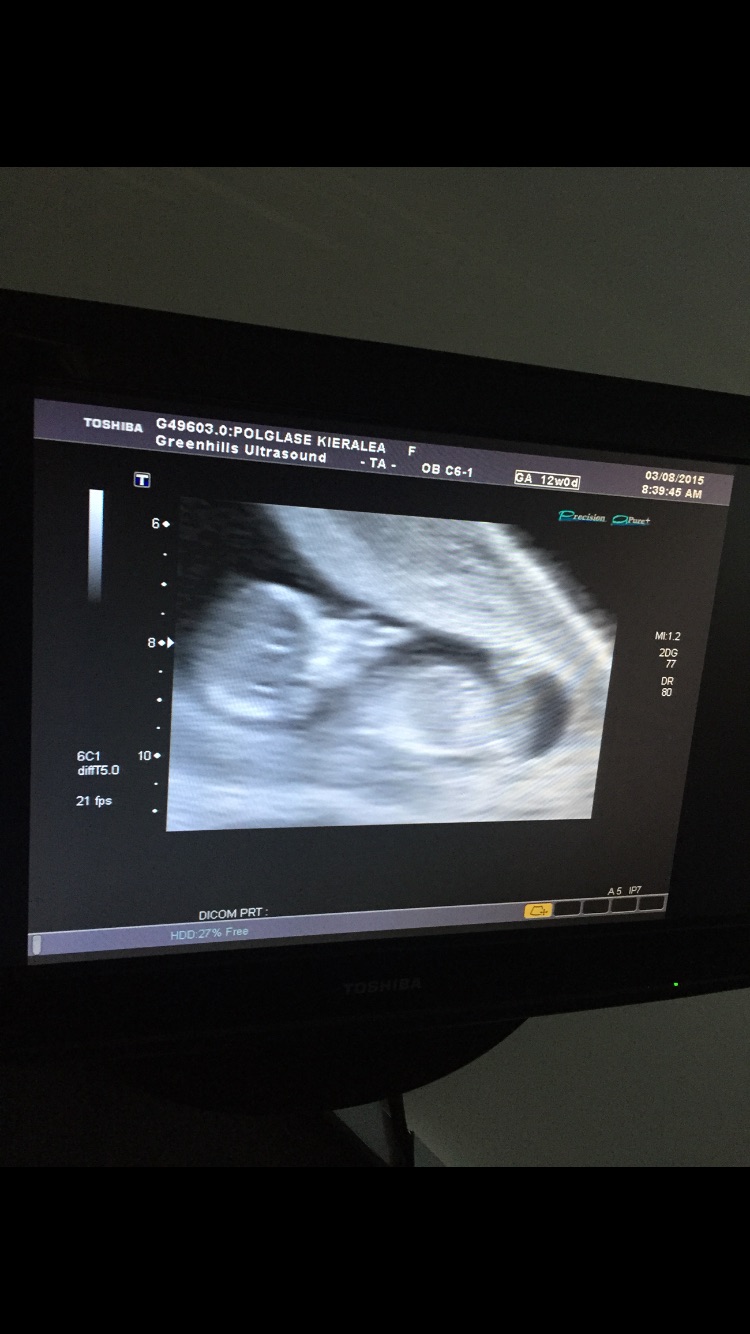

Our little one at 13 weeks 1 day! I didn't know you could have Braxton Hicks contractions this early - but apparently I was having one and it left baby a little squished and made it hard to get a good pic. Tech tried her best though! Loved seeing baby actually looking like a baby (instead of just a peanut) these days